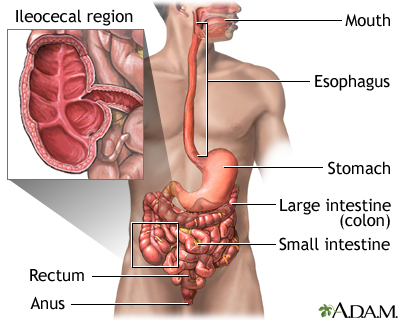

Crohn disease is a disease where parts of the digestive tract become inflamed.

- It most often involves the lower end of the small intestine and the beginning of the large intestine.

- It may also occur in any part of the digestive system from the mouth to the end of the rectum (anus).